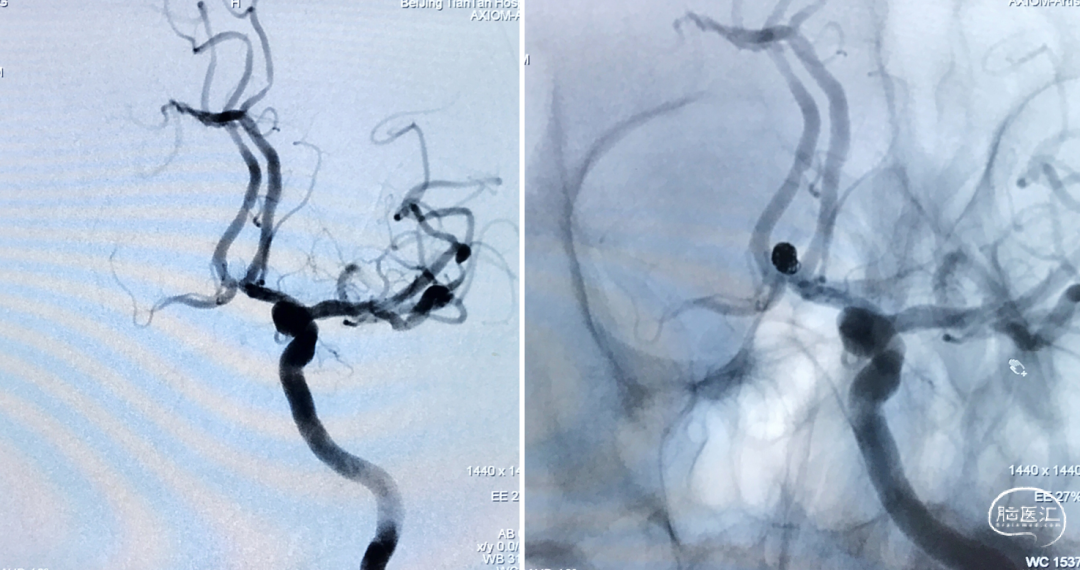

动脉瘤形态如下图,为前交通相对宽颈动脉瘤:

根据造影结果诊断为前交通动脉瘤

观察动脉瘤位于前交通动脉,形态较规则,相对宽颈,测量得直径约3.3mm,计划通过球囊辅助弹簧圈栓塞方式对动脉瘤进行致密栓塞

术前造影

术前工作位造影

术后造影显示,动脉瘤完全栓塞,Rayond分级-1